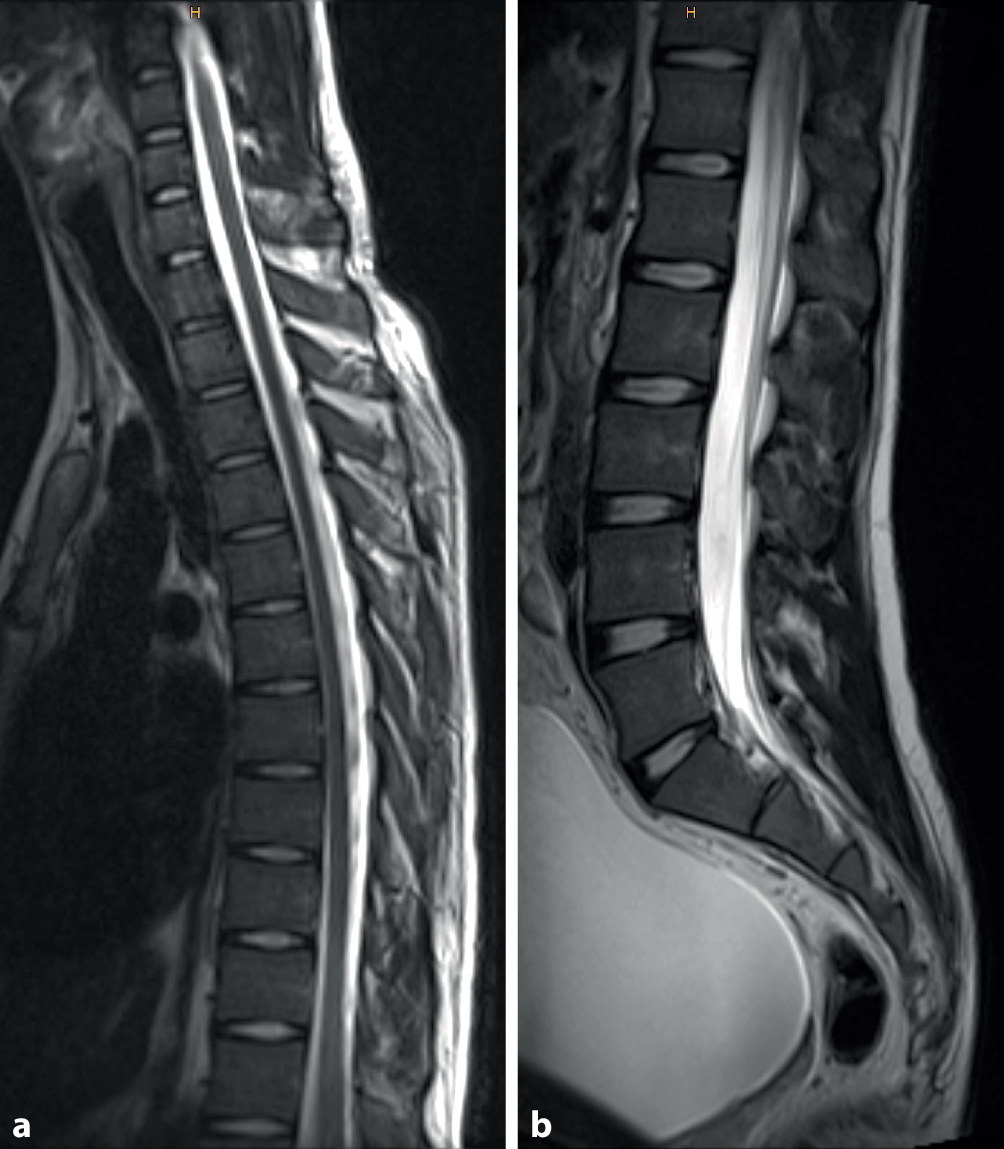

Das in weiterer Folge eingeholte psychiatrische Konsil ergab die Verdachtsdiagnose einer psychogenen Plegie (F44.4) unter Vorbehalt der noch ausstehenden weiterführenden bildgebenden Abklärung. Die im Anschluss durchgeführte Magnetresonanztomographie der gesamten Wirbelsäule ergab ebenfalls keinen pathologischen Befund (siehe Abb. 1). Nach Mitteilung des unauffälligen Befundes erhob sich der Patient von der Liege, tätigte problemlos einige Schritte im Ambulanzbereich und gab eine vollständige Remission seiner Symptome inklusive Wiedererlangen der willkürlichen Miktion an. Der Patient wurde schließlich, nach Vereinbarung eines Kontrolltermins an der psychiatrischen Ambulanz nach Rücksprache mit den behandelnden Psychiatern, entlassen. Rückblickend betrachtet war insbesondere die vollständige Anästhesie der beiden unteren Extremitäten auch unter Prüfung mit spitzer Nadel im Bereich der Fußsohle und der Harnverhalt bei beträchtlich gefüllter Harnblase (Abb. 1b) besonders eindrücklich.

Abb. 1

Unauffällige magnetresonanztomographische Darstellung in der T2-Turbo-Spin-Echo-Sequenz der unteren Hals- und gesamten Brustwirbelsäule (a) sowie der gesamten Lendenwirbelsäule bei prall gefüllter Harnblase (b). Intaktes Myelon im Bereich der unteren Halswirbelsäule, sowie der Brust- und Lendenwirbelsäule (a, b)